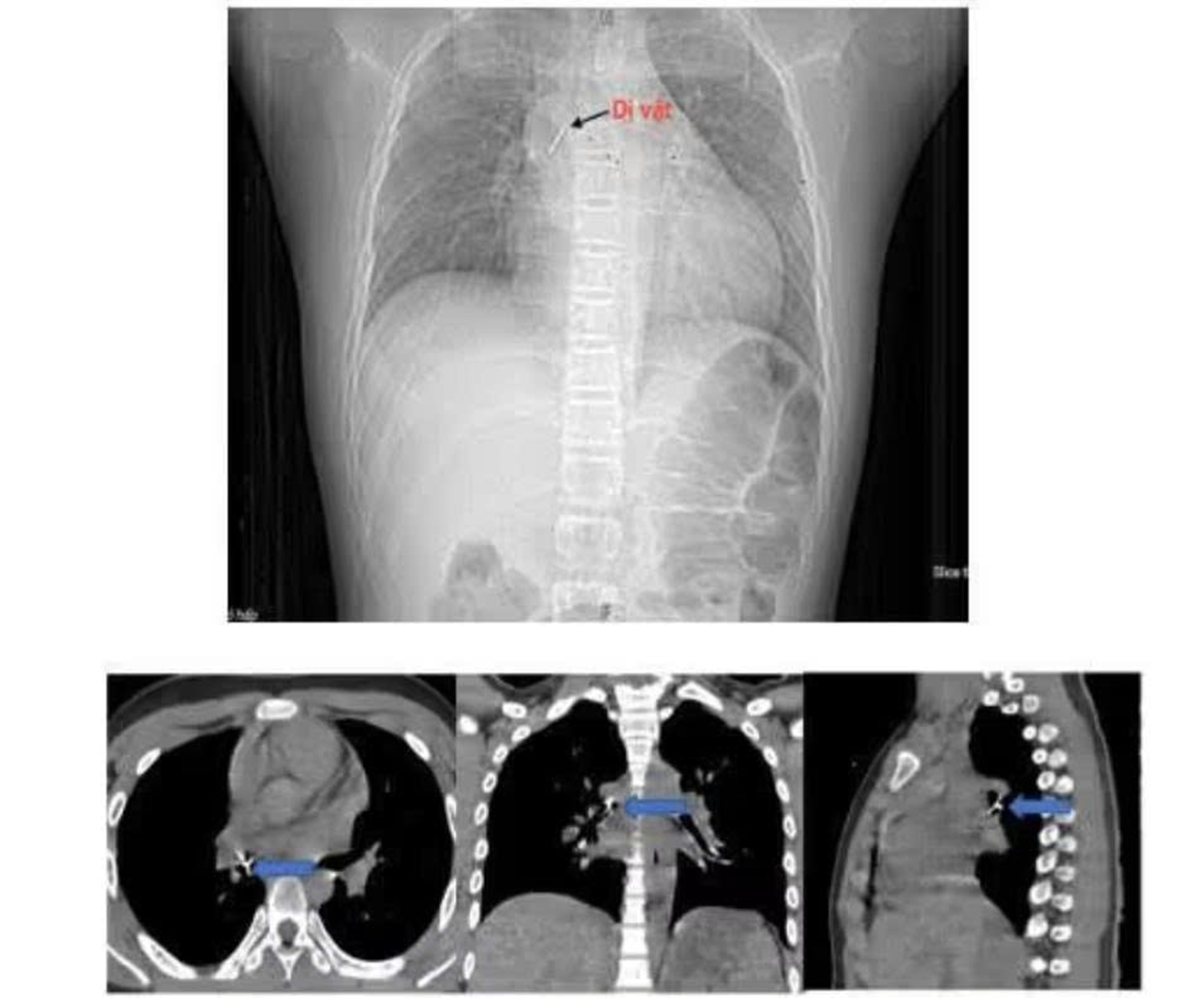

Ngay lập tức, gia đình đưa bé tới bệnh viện gần nhà. Sau chẩn đoán bằng chụp cắt lớp vi tính lồng ngực và nội soi phế quản ống mềm, các bác sĩ xác định dị vật nằm sâu tại phế quản trung gian bên phải, đầu ghim đã đâm xuyên vào thành phế quản gây chảy máu và phù nề.

Hình ảnh nội soi ống mềm gắp dị vật đinh ghim xuyên thành phế quản trung gian. Ảnh: BVCC